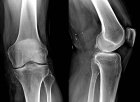

59 year old male c/o left calf swelling

Zoom image: Radiological image Radiological image.